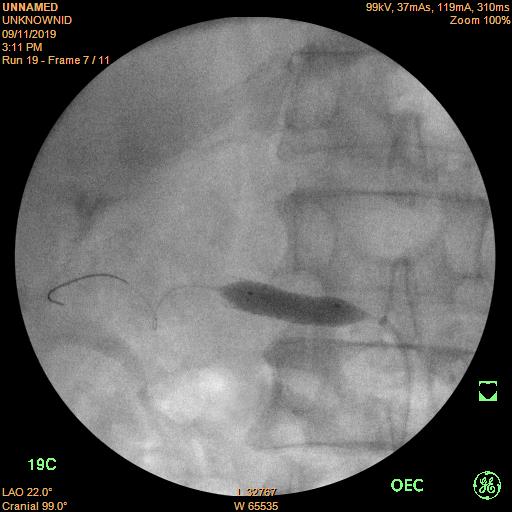

Sau khi hội chẩn, kíp can thiệp đã quyết định đặt stent (giá đỡ bằng kim loại) để nong vị trí hẹp, do kích thước động mạch thận phải rất lớn nên đơn vị can thiệp tim mạch bệnh viện Trường Đại học Y Dược Huế đã chọn stent động mạch thận phải lớn nhất là 7mm, vị trí đặt khá khó do gần gốc động mạch thận. Sau khi đặt stent kích thước động mạch thận phải trở lại bình thường.

Sau khi nong bằng bóng để làm nở vị trí hẹp, một stent kích thước 7.0x19 mm được đặt vào vị trí hẹp, chụp mạch máu thấy dòng chảy tốt, vị trí hẹp động mạch thận trước đây đã trở lại kích thước bình thường.

Hình 2. Đặt stent động mạch thận phải